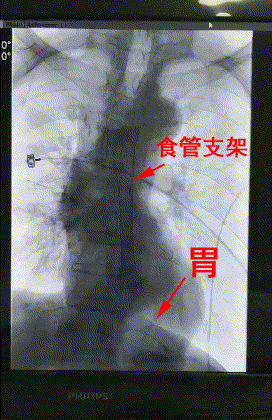

3月28日上午,楊阿姨被送進了介入手術室,李旭丹主任等專家根據術前方案上台施術,先采用飛利浦DSA開展食道造影,明确食道狹窄端及瘘口位置,後經導絲引入食管支架釋放于準确位置。DSA顯示支架成功擴張食管狹窄端并封閉瘘口,順利完成手術。

術後患者無不良反應,生命體征平穩,24小時後能夠進食。楊阿姨及其家屬非常感激。

△術後DSA造影顯示:支架成功擴張食管狹窄端并封閉瘘口。